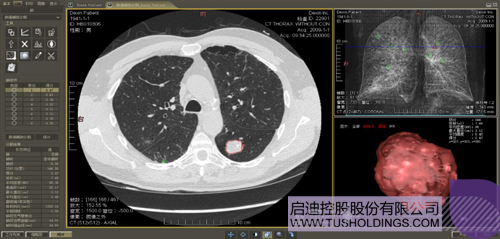

醫療影像智能分析是指運用人工智能技術、計算機視覺技術以及計算幾何技術對醫療影像進行自動分析,幫助醫生定位病癥、分析、跟蹤病情,并通過量化數據輔助醫生做出診斷,目前其旗艦產品“數字肺”已經覆蓋多種肺部疾病的早期檢測、診斷、跟蹤、術前規劃等完整的醫療流程。在臨床實踐中,超過80%的醫療數據來自醫療影像,這些影像數據通常需要專業醫生進行解讀,工作的重復性高、效率偏低。如果能夠運用智能影像分析技術,同時結合臨床表現以及既往病例進行全面分析,那么就可以大幅度提升影像診斷效率和準確性,讓專業醫生的寶貴時間集中在復雜病情的診斷和治療等環節。

肺動脈栓塞輔助診斷